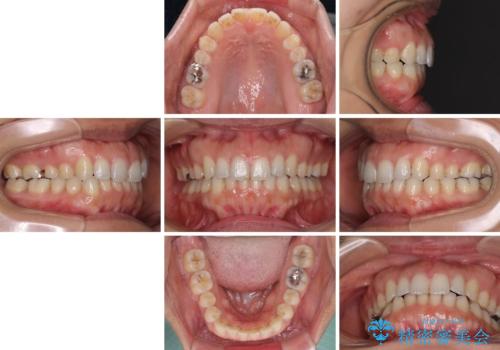

舌癖を改善したことで、隙間や突出感を改善することができました。

隙間は後戻りしやすいため、舌側を細いワイヤーで固定することとしました。